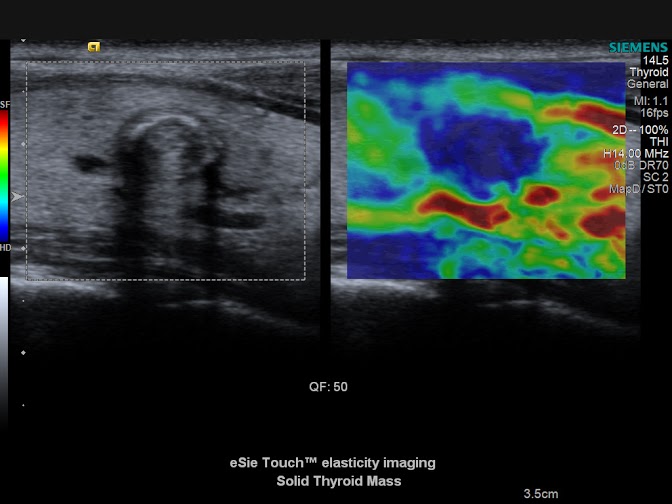

20130827105141015